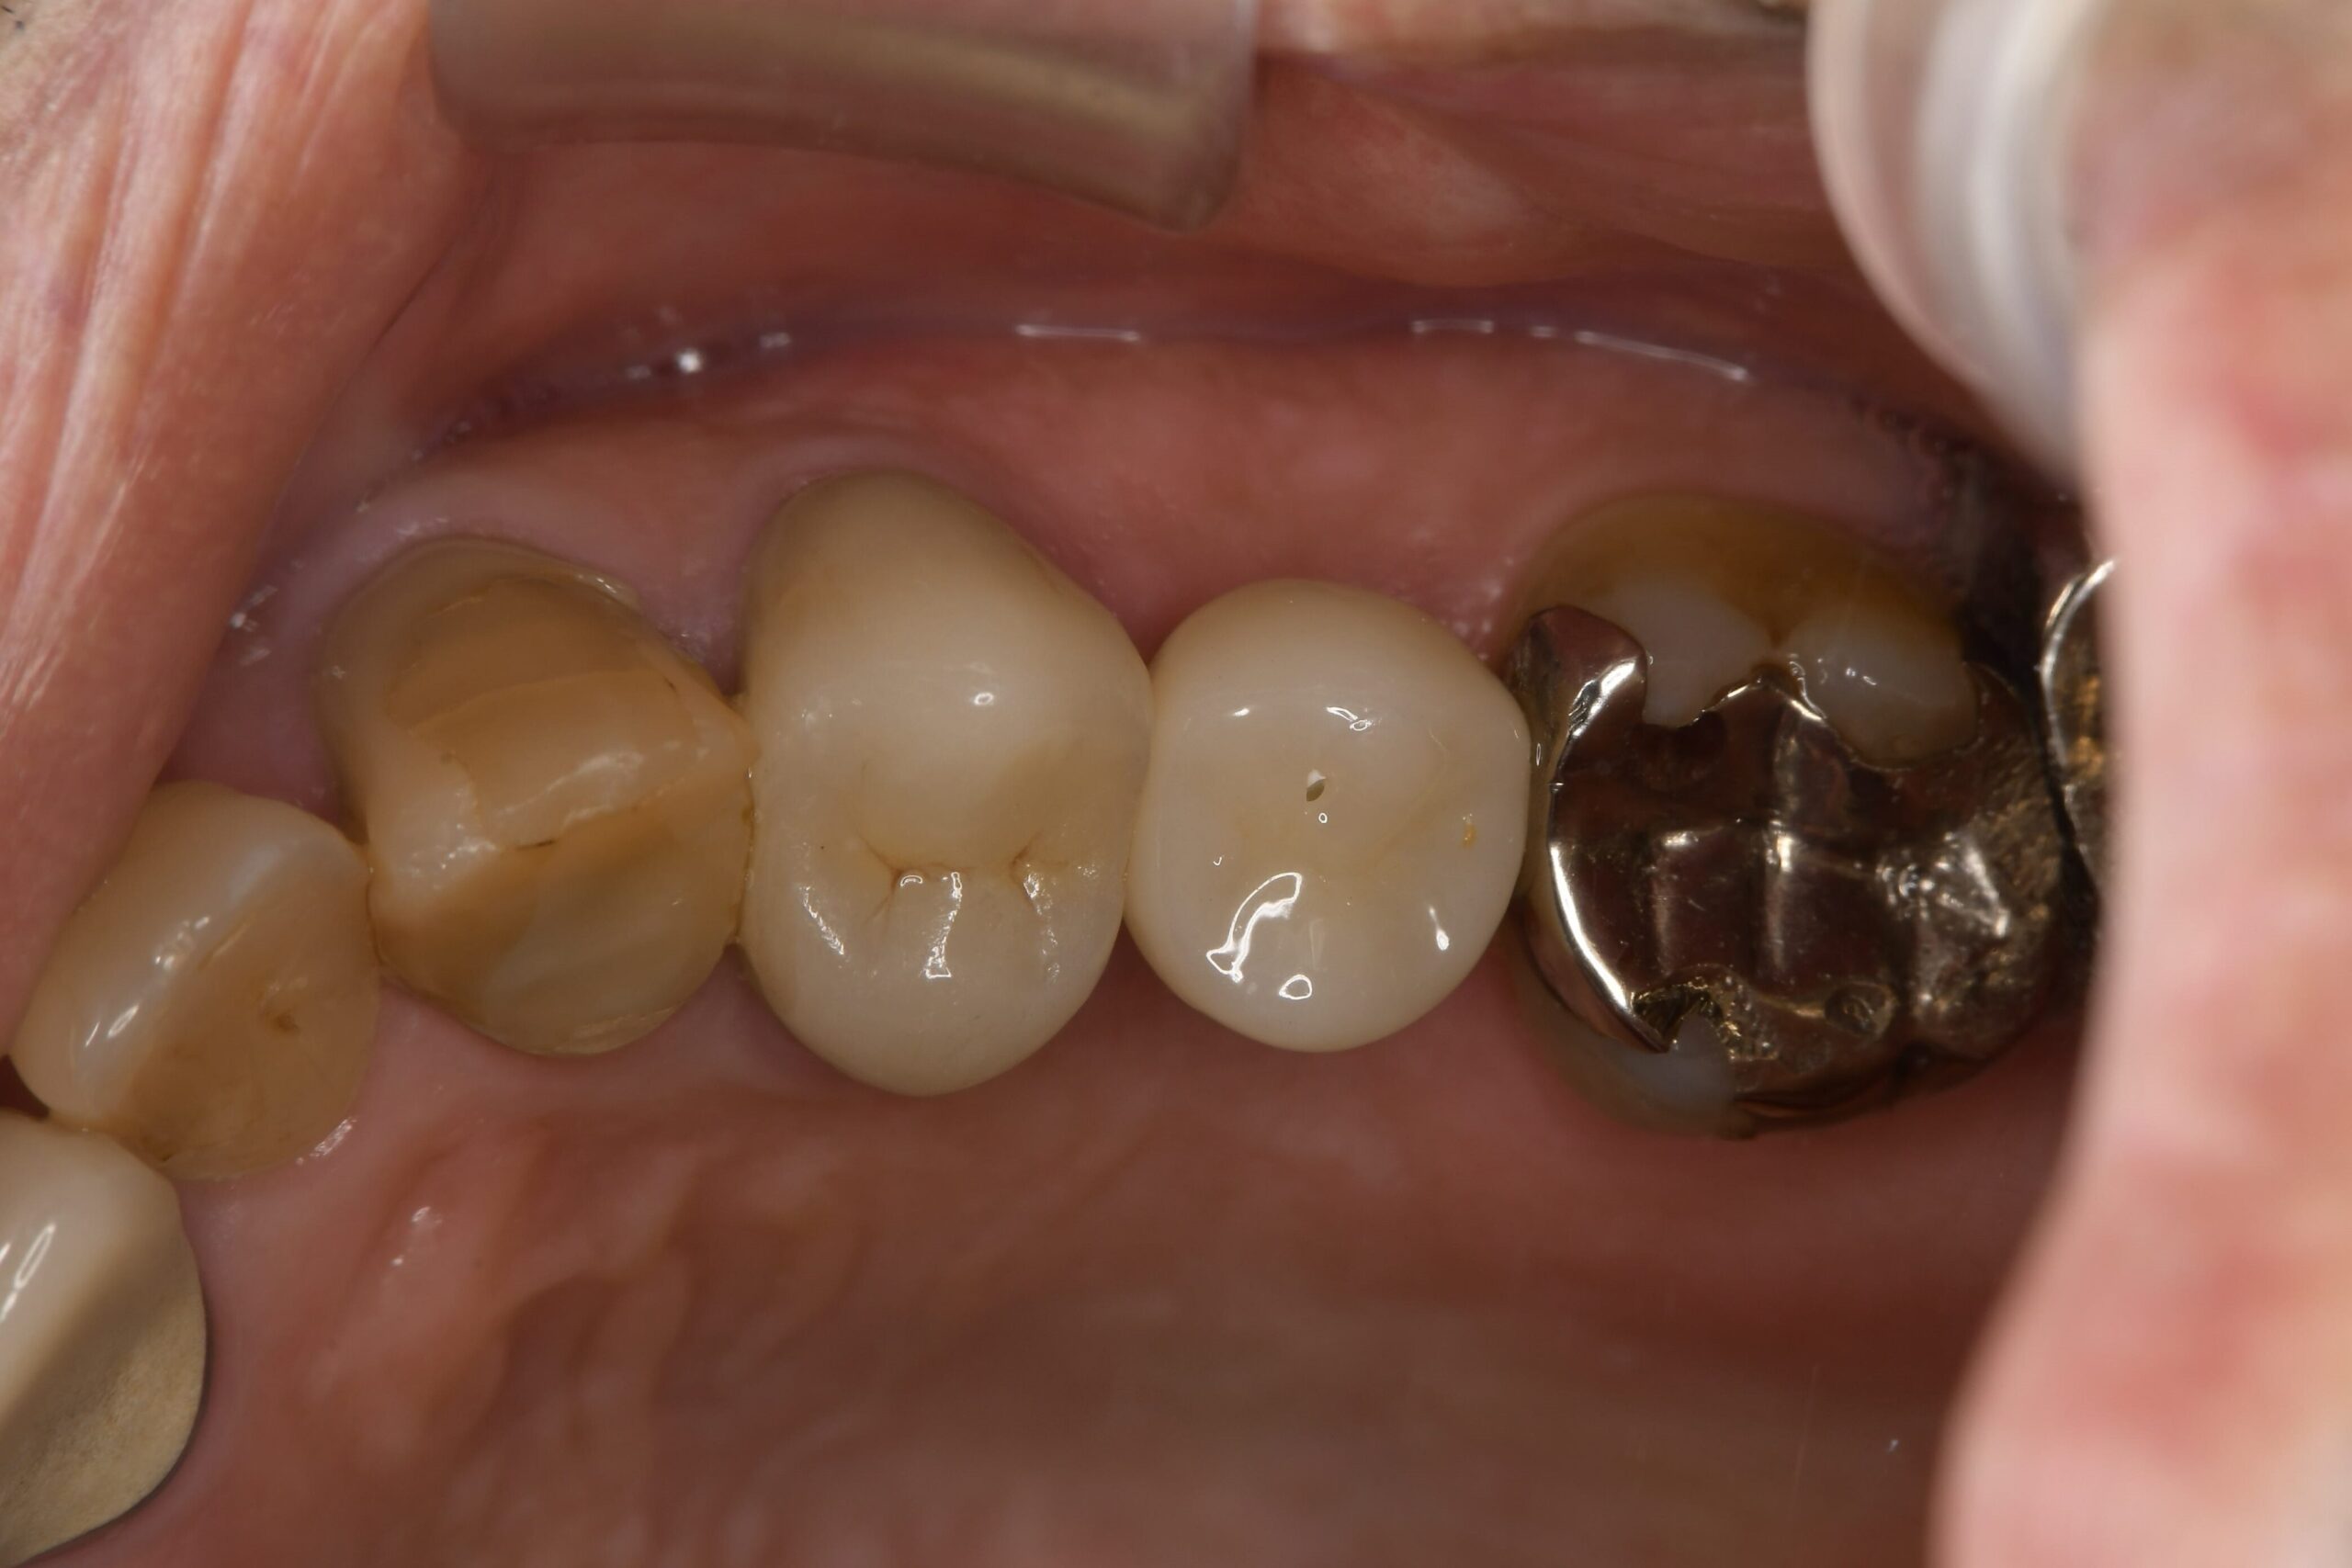

手術から約3~4ヶ月後、インプラントと骨がしっかりと結合していることを確認し、最終的な被せ物(上部構造)をセットしました。

●治療期間: 初診から約4ヶ月(通常法なら1年以上かかるところ)

●費用面: 骨造成(サイナスリフト等)の追加費用がかからず、トータルコストを抑えることができました。